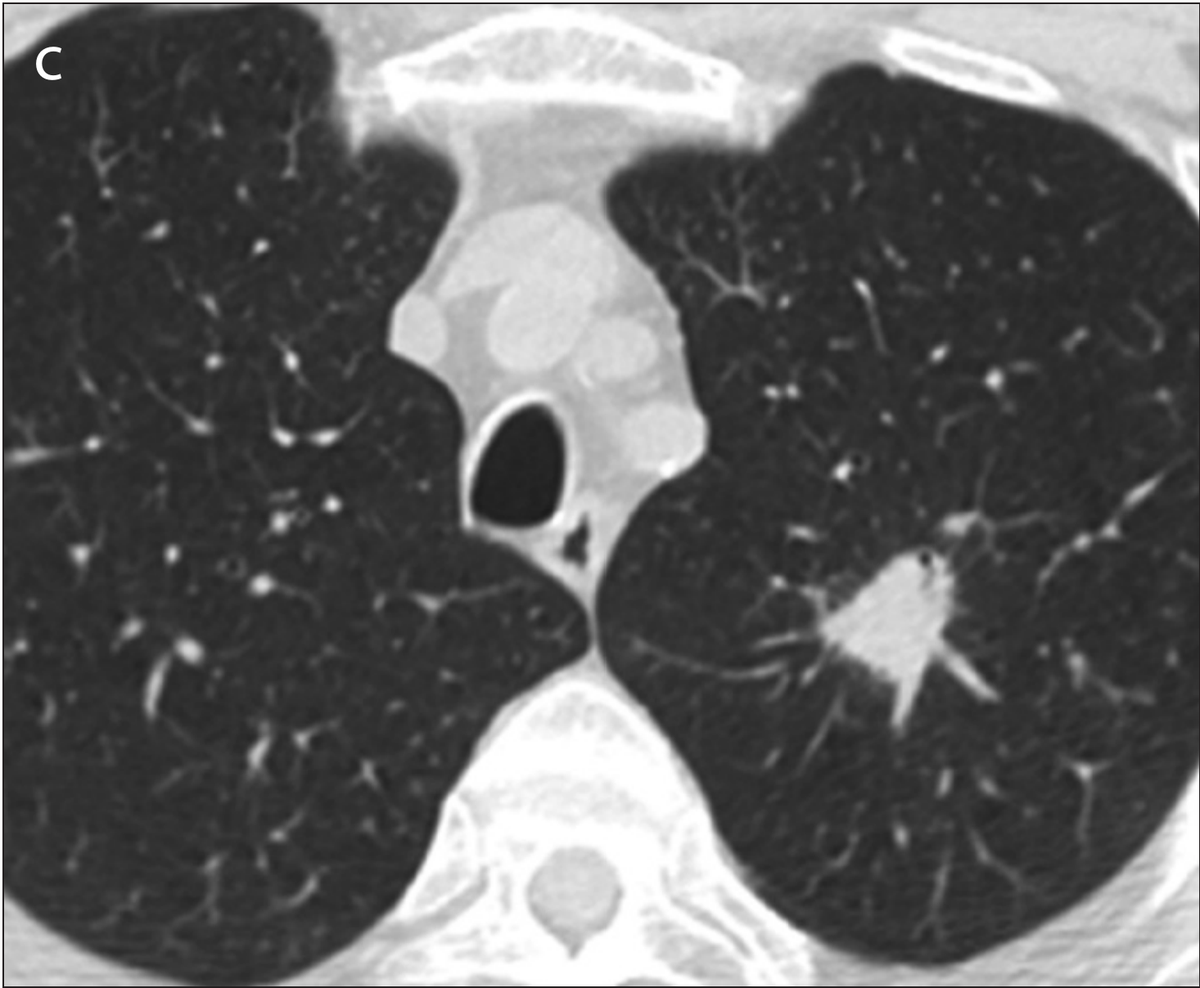

Example 2 shows an example CT scan of a 63-year-old with some of the characteristics described above. The nodule in the scan is small and close to a group of vessels of the upper left lung that partially block it from view, which caused the radiologist reading the scan to miss the tumor. The tumor was detected using a chest x-ray two years later.

Example 2: 63 year old patient with a cancerous lung nodule